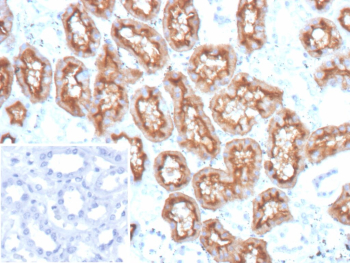

IHC staining of FFPE human kidney tissue with MME/CD10 antibody (clone MME/12957R). Membranous and luminal staining is observed in renal proximal tubular epithelial cells, consistent with known CD10 expression, while surrounding interstitial cells show minimal staining. Inset: PBS used instead of primary antibody as a negative control. Heat-induced epitope retrieval was performed by boiling sections in pH 9 10 mM Tris with 1 mM EDTA for 45 min at 95oC followed by cooling at RT for 20 min.